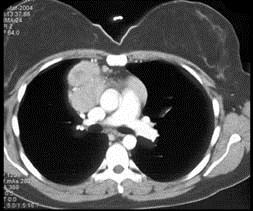

问题 女,27岁,双侧颈部淋巴结肿大,PPD(-),请结合CT图像,选择最可能的诊断 ( )

选项 A.心包囊肿 B.淋巴瘤 C.淋巴结核 D.转移性淋巴结肿大 E.结节病

答案 B